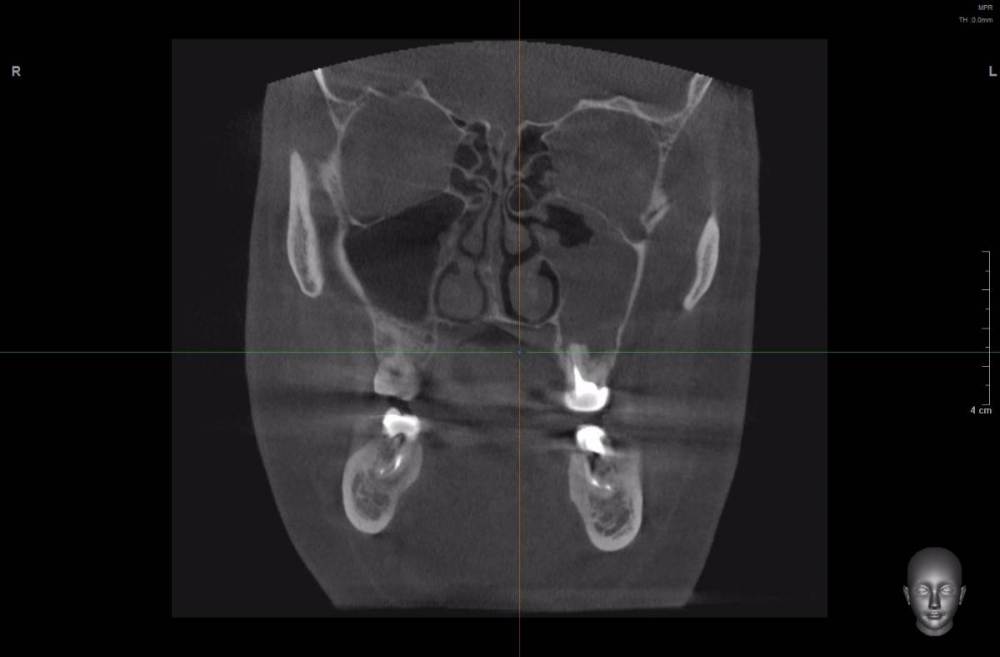

wladdX Опубликовано 22 марта, 2021 Поделиться Опубликовано 22 марта, 2021 При изучении КЛКТ, сделанной по другому поводу, обнаружил радикулярную кисту с врастанием в в/чел синус, размерами около 3*3*3см. Костных стенок кроме нижней и медиальной уже нет. Скрытый текст Как к этому делу подступиться правильно? Ссылка на комментарий

kriokov Опубликовано 23 марта, 2021 Поделиться Опубликовано 23 марта, 2021 3 часа назад, red_butler сказал: имхо, нужно через ЛОРа соустье по фронтальному срезу рабочим выглядит. Видно хорошо деформацию латеральной стенки по сравнению с противоположной стороной. Нет грубой деструкции. Удалить зубы причинные, цистэктомия , окно доступа закрыть мембраной или титаном. Ссылка на комментарий